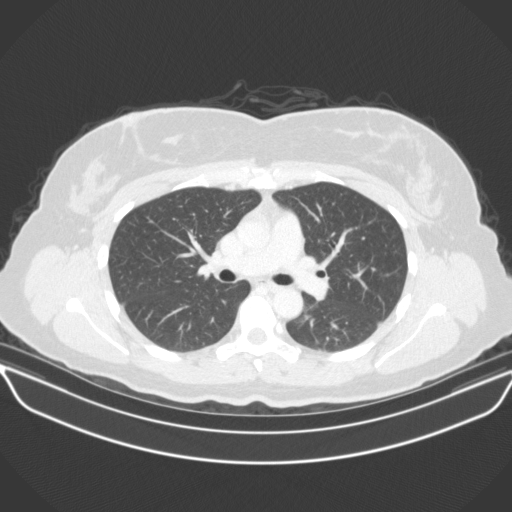

Image Grid

4Γ—3 grid: Rows show different image types (Original NATIVE, Reconstructed NATIVE, Original VENOUS, Generated VENOUS), Columns show windowing techniques (No Window, Lung Window, Mediastinum Window)

Lung window (WL -600, WW 1500 β†’ Low βˆ’1350, High +150)